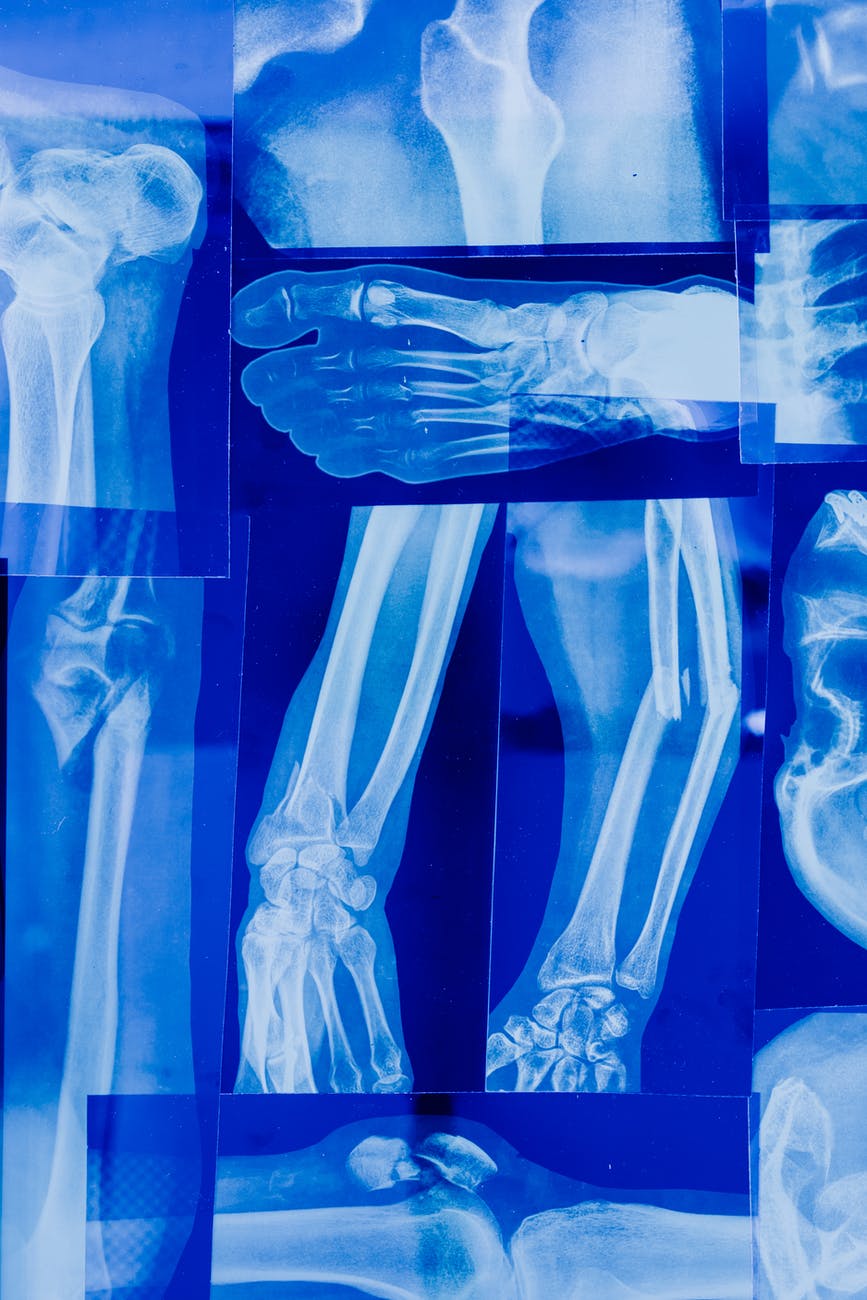

Η οστεοπόρωση είναι μια ασθένεια που συνοδεύει συχνά την γήρανση, αλλά αρχίζει ύπουλα από τα 20 χρόνια μας. Χαρακτηρίζεται από μείωση τόσο στης οστικής μάζας όσο και της ποιότητας των οστών. Υπολογίζεται ότι μια στις τρεις γυναίκες και ένας στους πέντε άνδρες άνω των πενήντα υποφέρουν από οστεοπορωτικά κατάγματα. Ας δούμε πρώτα τι ακριβώς είναι η οστεοπόρωση και μετά τι μπορούμε να κάνουμε για να την αντιμετωπίσουμε